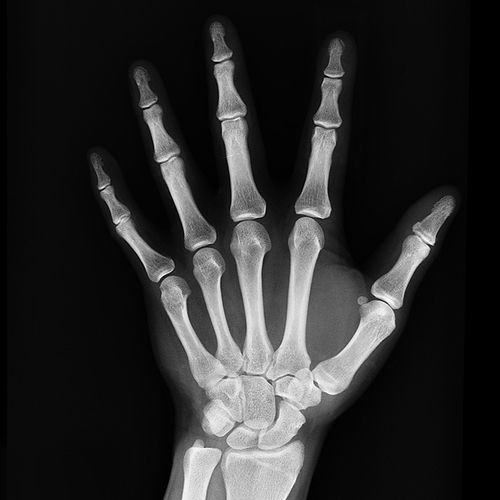

Creighton University doctors regularly recommend that aging women take calcium and vitamin D supplements to help reduce their risk of broken bones and osteoporosis. But even short periods of supplementation may reduce the risk of stress fractures in younger women. So concludes a new study of 5.200 female US Navy recruits going through basic training. Half of the women—ages 17 to 35—were given daily vitamin supplements of 2,000 milligrams of calcium and 800 international units of vitamin D. The others received placebo pills.

After eight weeks, researchers noted stress fractures in 170 recruits. These overuse injuries were 25% more common in those taking the dummy pills. Not surprisingly, researchers also noted that smoking increased bone injury risk, while a history of exercise decreased the risk.

Vitamin D helps the body absorb calcium, which is vital to bone formation and repair.

"What really surprised us is that calcium/vita-min D supplements made a significant difference in such a short period of time," says study lead Joan Lappe, a professor of nursing and medicine at Creighton University in Omaha, Nebraska. "Frankly, we were not sure we would sec any sta-tistically significant results in only eight weeks." Bottom line: Although these findings are preliminary, they could help reduce bone injuries in high school and other amateur athletes.